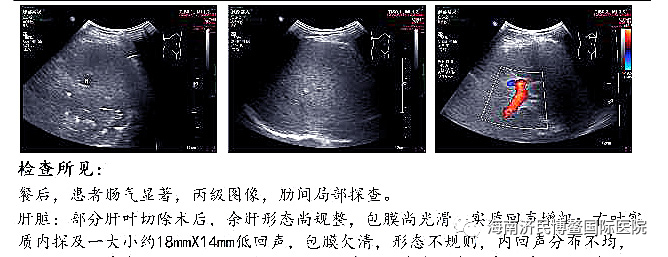

未治疗前,吴先生两个肝脏布满大大小小的“牛眼”征病灶,最大病灶达10公分,但经过博鳌国际医院3个月4个疗程的综合治疗,满布肝脏大大小小的病灶已经全部消失,只剩下一个原先最大10公分病灶已缩小至1.8公分,并且萎缩坏死液化,几乎没有活性。

治疗后:7月17日最大肿瘤病灶体积18mm*14mm